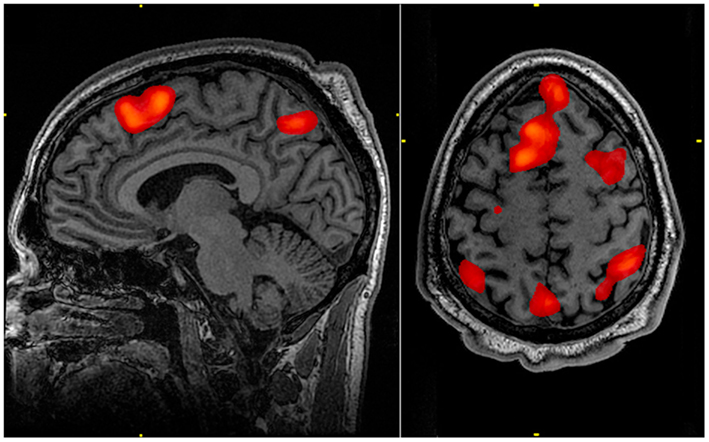

Ce processus est appelé hyperactivation (plus) ou hypoactivation (moins). L'hyperactivation peut être détectée sur les IRMf lorsque des zones du cerveau sont surlignées en rouge et que l'hypoactivation est indiquée par des zones bleues.

L'IRMf cartographie ensuite les zones activées à l'aide de voxels (lors de la création d'une image 3D du cerveau, une unité de voxel représente une minuscule portion de tissu cérébral dans l'image), produisant ainsi des images neuronales.

Les zones mises en évidence sont des parties actives du cerveau.

Par exemple, certaines zones du cerveau apparaissent lorsqu'une personne travaille sur une tâche de mémoire.

Résonance magnétique fonctionnelle IRMf mémoire de travail StudySmarterFig. 2 : Un examen IRMf réalisé au cours d'une tâche de mémoire de travail révèle les zones actives du cerveau.